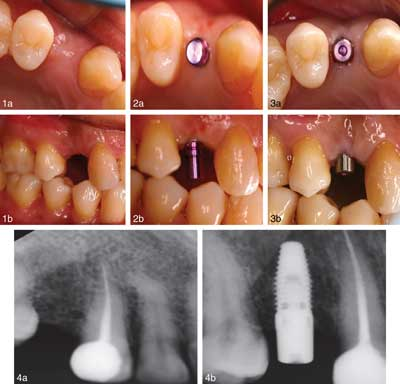

CASE 1Patient 1.Figure 1. Occlusal and lateral view before the procedure. Figure 2. Occlusal and lateral view of the direction indicator placed during the surgery showing minimal bleeding. Figure 3. (a) Occlusal view of the healing abutment in place immediately after implant insertion. (b). Lateral view of the direction indicator placed during the surgery. Figure 4. Digital periapical radiographic view before and after implant placement.